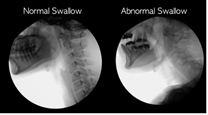

Dysphagia videofluoroscopy

Explanation about Dysphagia